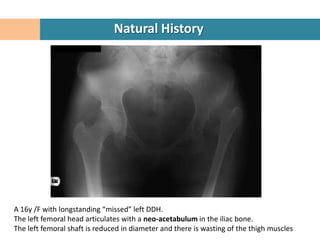

A 16y /F with longstanding “missed” left DDH.

The left femoral head articulates with a neo-acetabulum in the iliac bone.

The left femoral shaft is reduced in diameter and there is wasting of the thigh muscles